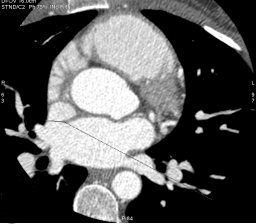

The CT Scanner, or the Diagnostic and Wellness Center, has been a major center of research and development in the field of coronary artery calcium and cardiac computed tomography angiography (CCTA). Helmed by Dr. Matthew Budoff, it holds one of the most experienced research teams in the world and has been performing CT interpretation and has paved the way for the role of CCTA in the noninvasive diagnosis of coronary artery disease and anatomical visualization for over 20 years.

As the Cardiology fellow on Advanced Imaging at Harbor-UCLA, you can:

- Participate in the acquisition and interpretation of coronary CTAs, over 100 of which are done monthly

- Gain exposure to multimodality advanced imaging, including when performed by Dr. Jina Chung

- Correlate findings from echocardiography, CT, angiography and cardiac MRI through image acquisition, case interpretation, and teaching conferences

- Explore research opportunities with the CCTA team

- Enroll and participate in the Cardiac CT Training Certification course run by Dr. Matthew Budoff